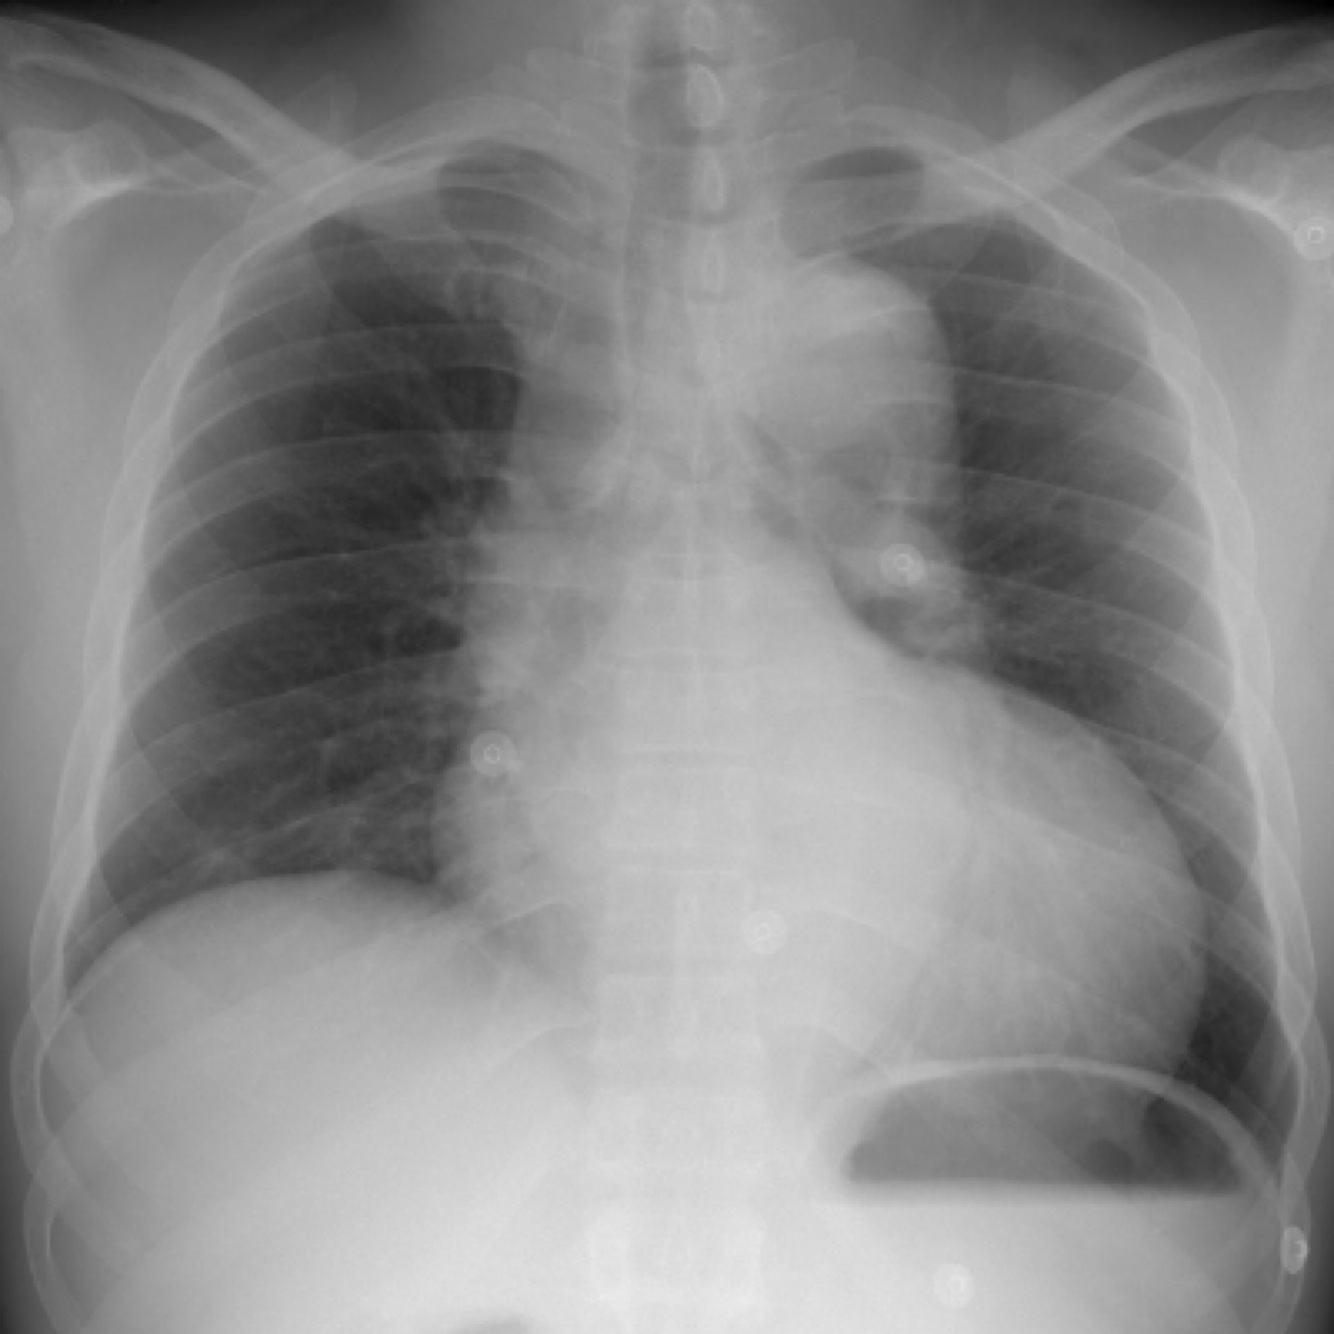

right pleural effusion shown on x-ray,